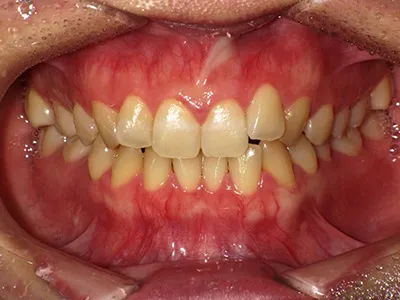

症例4

before

after

| 主訴 | 八重歯が気になる、歯並びきれいにしたい |

|---|---|

| 治療内容 | ワイヤー矯正 |

| 治療期間 | 1年 |

| 費用 | 770,000円(税込) |

| リスク・副作用 | 歯牙移動による痛み、染みる症状が出てしまうことがあります |